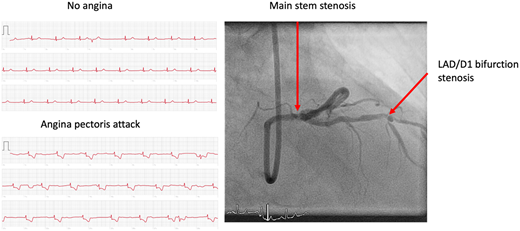

ผู้ป่วยจึงได้นำผลที่วัดคลื่นไฟฟ้าหัวใจด้วย Apple Watch มาให้แพทย์ดู พบว่ามีสัญญาณของภาวะกล้ามเนื้อหัวใจขาดเลือด แพทย์จึงได้โอนย้ายผู้ป่วยไปยังแล็บการสวนหัวใจและหลอดเลือด พบว่าหลอดเลือดตีบที่โคนของหลอดเลือดข้างซ้ายและแตกออกไปเป็นแขนง LAD/D1 bifurction stenosis